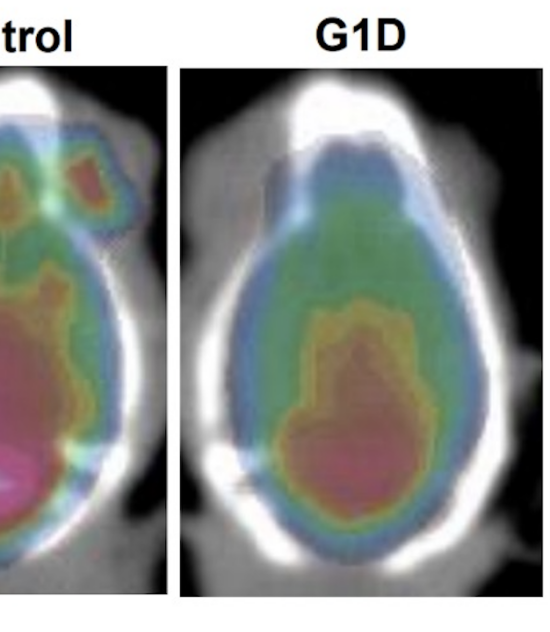

Los glóbulos rojos como transportadores de glucosa al cerebro humano

Los hematíes como transportadores de glucosa al cerebro humano: Modulación de la actividad cerebral por